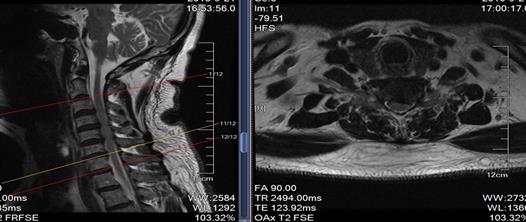

来自大连的张大爷(化名)备受颈椎病的折磨,左上肢麻木疼痛难忍,去过好几家医院都说让开放手术,张大爷很恐惧,经多方打听了解到我们医院能做微创手术就来我院就诊,我们给他做了颈椎椎间孔镜手术。

术后患者症状明显减轻,张大爷终于可以睡个好觉了。